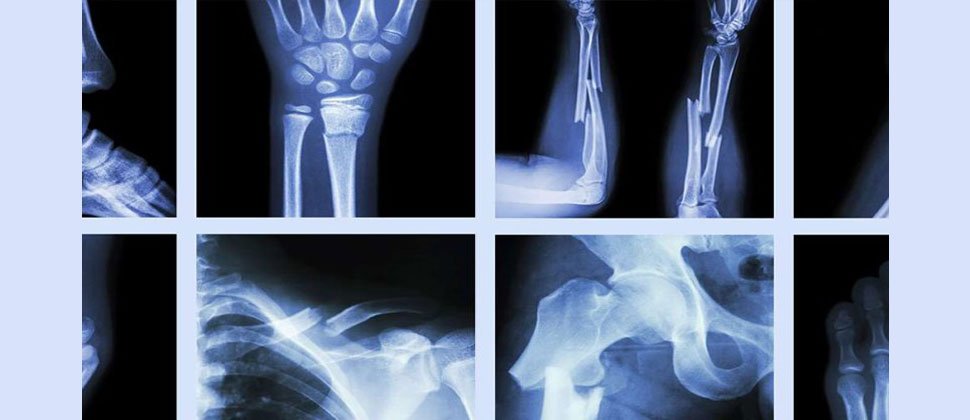

Orthopaedics & Joint Surgery

The orthopaedics department at Srijan Hospital provides extensive solutions for a wide range of orthopaedic disorders of bones, joints, ligaments and muscles. The department offers high-quality amenities to all ages for simple as well as complex fractures and dislocations. Also available are pain-relief solutions for arthritis, degenerative diseases or trauma to the joint. Special attention is placed on diagnostic & therapeutic orthopaedic, arthroscopic and joint replacement surgeries for all, including geriatric patients. Facilities available are modular orthopaedic operation theatre, digital & mobile X-Ray and 2 Slice Spiral C.T. Scanner.